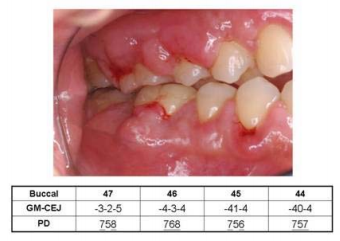

75. 王先生因刷牙流血而來醫院牙周病科求診,經臨床檢查後發現病人有多處牙齦腫大的情形,詢問 全身性病史得知病人有高血壓,且目前正服用藥物控制中,臨床照片如下圖所示,下列敘述何者 正確?(GM-CEJ:gingival margin-cementoenamel junction,PD:probing depth,數字下畫線 代表探測流血)

(A)若進行牙周治療時,為了控制局部流血情形可使用含1:100,000濃度的epinephrine麻藥控制 (B)如圖所示誘發牙齦腫大的情形,可能是服用鈣離子阻斷劑降血壓藥物許久的結果所致 (C)右下側後牙牙齦腫大的情形,頰側均有≧5 mm的牙周組織臨床附連喪失 (D)其治療計畫可先會診內科醫師建議更換服用藥物後,再直接以牙周手術方式來改善牙齦腫大的 問題